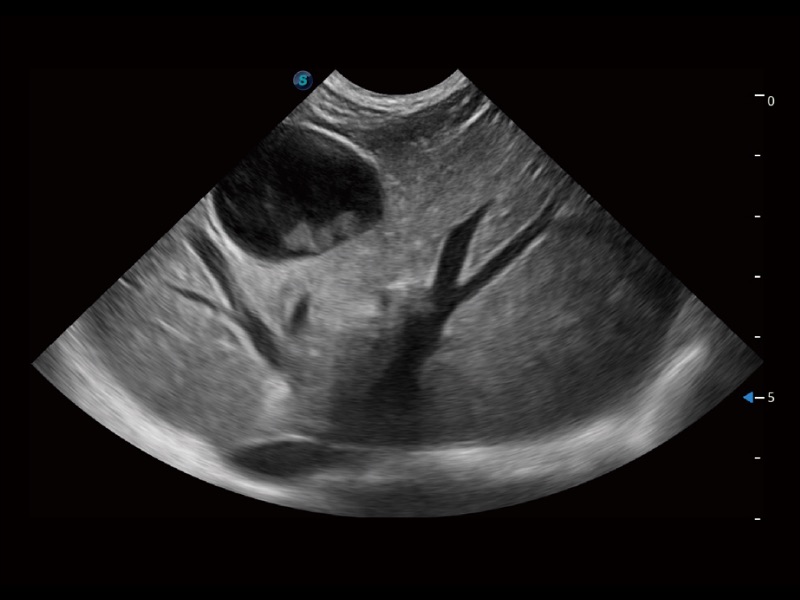

(犬)胎儿主动脉弓立体血流

(犬)肝脏